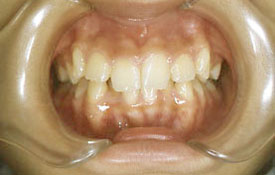

インビザラインの治療例:CASE-1

| プロフィール | 42歳 女性 |

| 所見 | 他院で行われた矯正歯科治療後の後戻りに悩まれて来院されました。 アイライナーの装着は、1日平均20時間ほどでした。 |